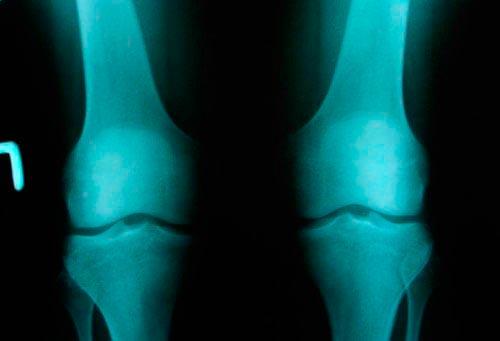

Статистические данные показывают, что гонартроз занимает лидирующие позиции среди прочих видов артроза, делающих из человека инвалидов. В медицине выделяют несколько степеней артроза. Их разделяют при помощи клинико-рентгенологической диагностики.

1 степень проявляется в виде незначительного нарушения подвижности сустава. Рентген показывает небольшое разрастание кости по краям впадины самого сустава, его щель сужена, имеются районы оссификации хрящевой ткани.

При артрозе коленного сустава 2 степени возникает грубый хруст при движении. Наблюдается общая невозможность передвигаться. При проведении рентгена видны большие области костных разрастаний, начинается субхондральный склероз, щель сустава сужается в два-три раза, по сравнению с показателями нормы.

Гонартроз коленного сустава 3 степени характеризуется утратой полноценного движения. Остаются только покачивания пораженным суставом. Он очень сильно деформируется. После рентгена можно увидеть отсутствие суставной щели. Сама поверхность расширена из-за разрастания ее краев. Деформирование остро выраженное, имеется уплотнение обоих эпифизов.

Гонартроз 1 степени диагностируется только в том случае, если на рентгенографии отчетливо заметно уменьшение зазора между костными поверхностями. При этом оно должно быть неравномерным. По краям сустава видны следы формирования остеофитов. Наблюдается слабое ограничение подвижности колена.

Артроз 2 степени характеризуется более выраженными изменениями. Для него характерны следующие признаки:

- щель между костями меньше нормы в 2 раза;

- остеофиты стали крупными;

- в отделе костной поверхности, контактирующей с хрящевой тканью, появляется остеосклероз.

Третья степень проявляется сильным ограничением подвижности. Пациент может лишь немного покачивать ногой в суставе. При этом отклонения в нем не превышают 7° от первоначального положения. На рентгене видны следующие изменения:

- значительное уплотнение костных поверхностей;

- колено сильно деформировано;

- остеофиты захватывают все суставные поверхности;

- щели между костями нет;

- видны субхондральные кисты;

- наличие в синовиальной полости остатков хряща.